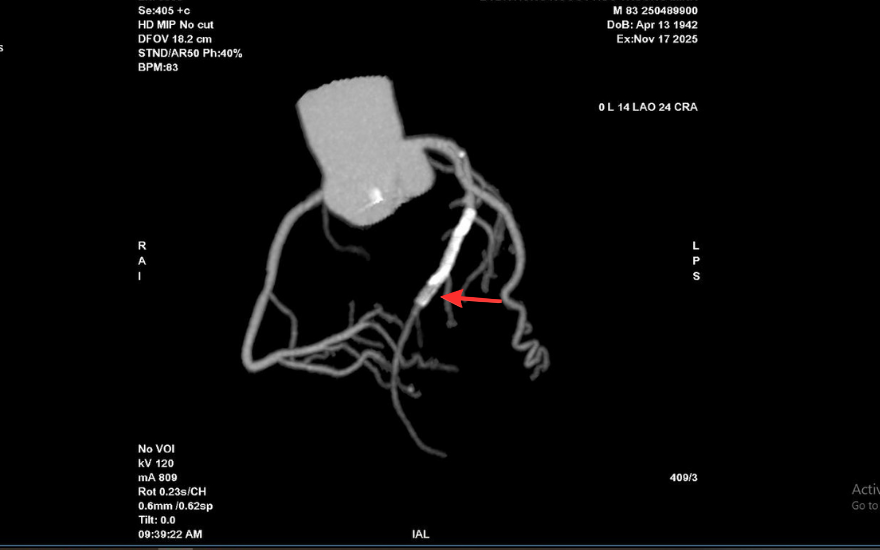

Tại BVĐK Hồng Ngọc, kết quả chụp CT 2560 lát cắt cho thấy tình trạng nghiêm trọng hơn nhiều so với biểu hiện ban đầu: mảng xơ vữa lan rộng gây hẹp nặng đoạn đầu động mạch liên thất trước và gần như làm tắc hoàn toàn lòng stent cũ. Đây là dấu hiệu cho thấy nguy cơ biến chứng tim mạch cấp tính có thể xảy ra bất cứ lúc nào nếu không được can thiệp kịp thời.

Vị trí hẹp khít trong lòng stent cũ của ông T trên hình chụp CT mạch vành 2560 lát cắt

Kết quả chụp mạch vành qua da trước can thiệp cho thấy mức độ tổn thương của ông T. nghiêm trọng hơn dự kiến. Lòng stent cũ tái hẹp tới 99%, trong khi đoạn mạch phía trước vị trí đặt stent cũng hẹp khoảng 90%, khiến dòng máu nuôi tim bị chậm đáng kể.